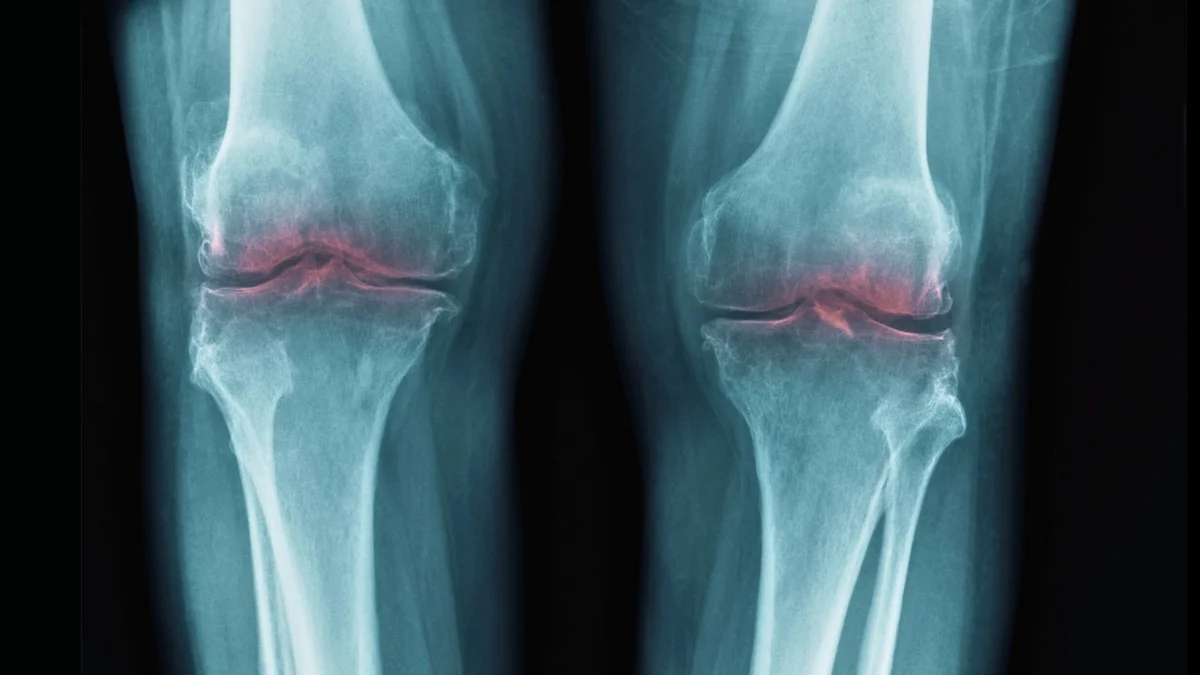

Scientists have shown in mice that inhibiting the aging enzyme 15-PGDH can regrow cartilage without stem cells, with treated cartilage thickening into hyaline cartilage and reprogramming existing joint cells to build tissue. Early tests on human cartilage also show reduced enzyme activity and initial matrix rebuilding, suggesting a potential, less invasive path to treating osteoarthritis, though research is in early stages.